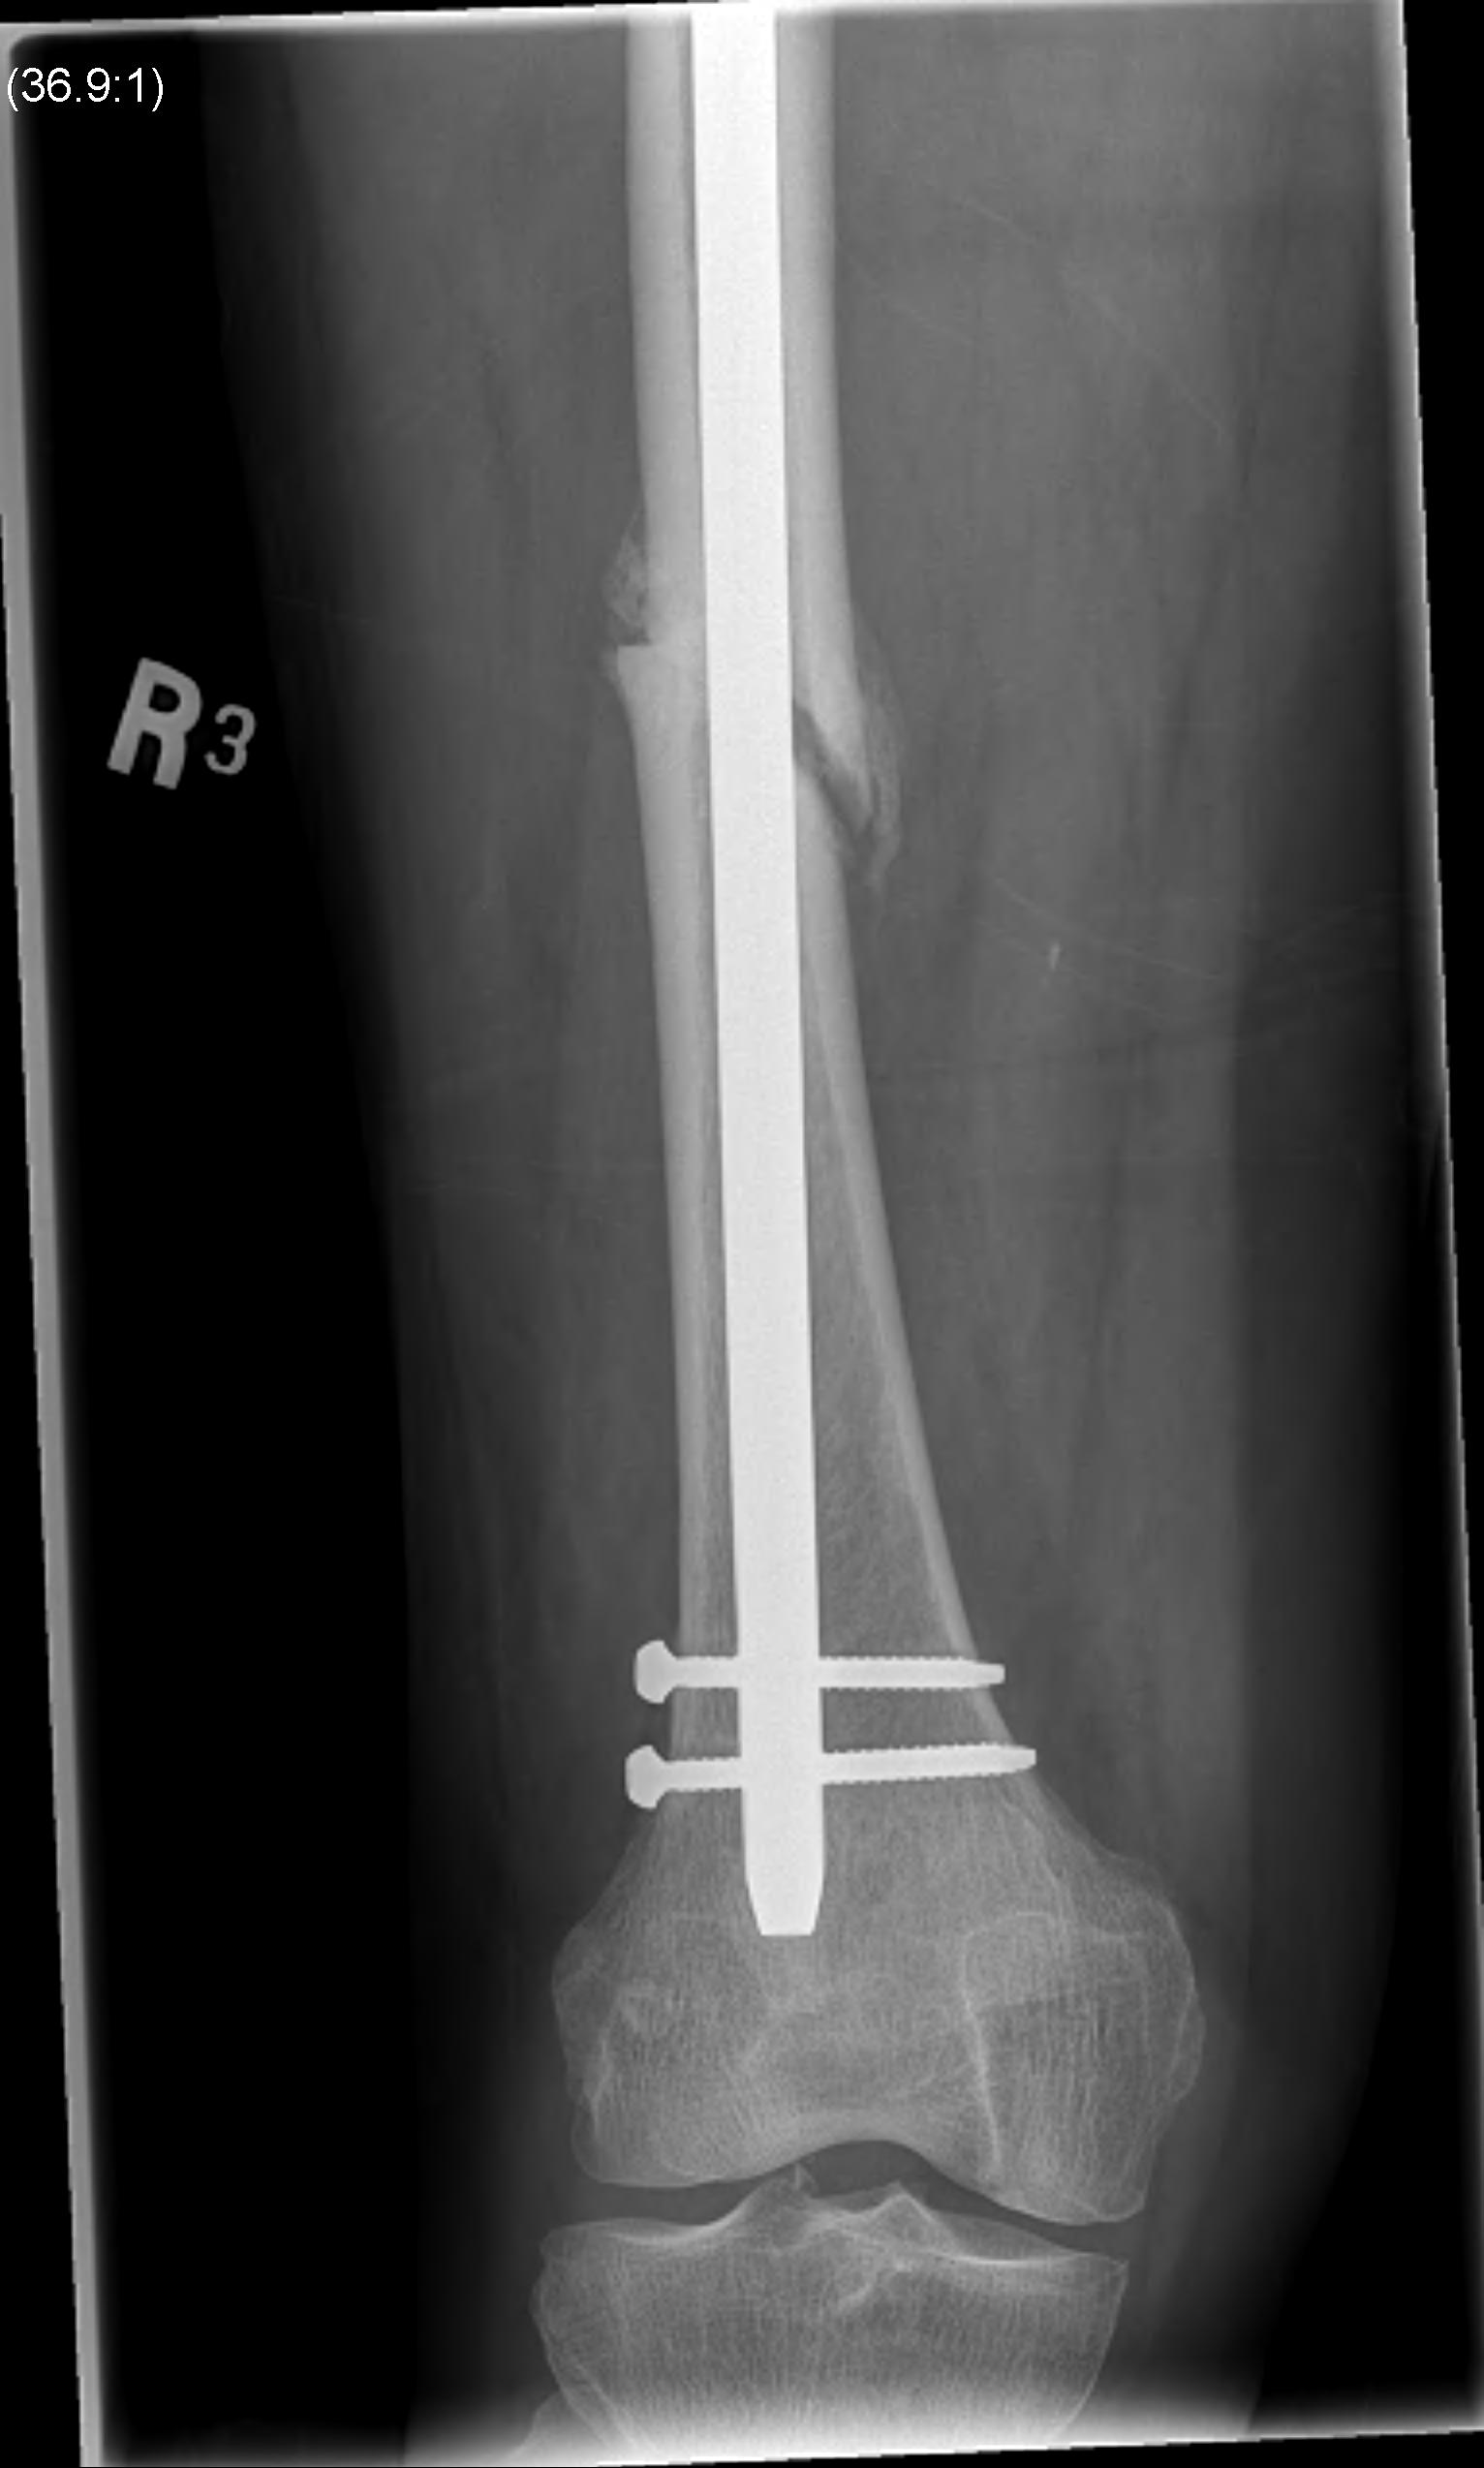

1. Floating Knee

Single incision at knee

- retrograde femoral nail

- tibial IMN if appropriate

High complication rates including non union / malunion, knee stiffness and hetertopic ossification

4. Distal femoral condylar fracture + shaft fracture

Options

1. Screws anterior and posterior to retrograde nail

2. Distal Locking plate